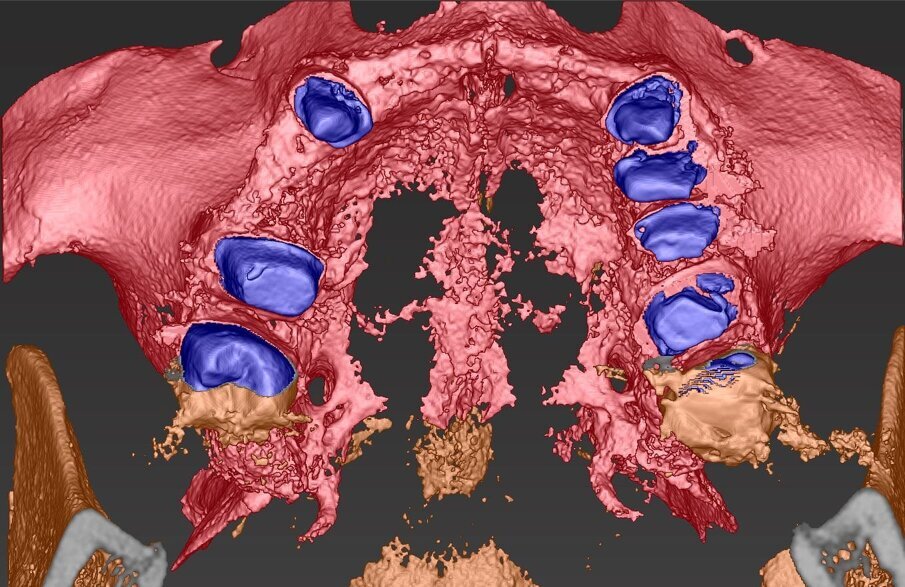

L’informazione diagnostica dettagliata è fornita dalla CBCT, pertanto abbiamo pianificato la sua esecuzione dopo la prima provvisorizzazione dell’arcata superiore evitando lo scattering da metalli presenti. Il file STL del wax-up (Fig. 6) associato al file STL dell’impronta senza provvisorio (Fig. 7) e al file DICOM radiologico (Figg. 8, 9) ha permesso una corretta progettazione chirurgico implantare (Fig. 10) nel rispetto della porzione ossea della cresta residua, ottimizzando la conseguente realizzazione della dima chirurgica (Fig. 11) per il posizionamento degli impianti in sede 1.2 e 2.2 (Figg. 12-14) anche nel rispetto della posizione degli elementi in antagonismo (Fig. 15). Il primo provvisorio avrà diverse funzioni tra cui la valutazione dell’inclinazione coronale, l’ingombro volumetrico e il supporto labiale del gruppo frontale per la correzione dell’emergenza del labbro superiore (Fig. 16). Dopo un breve periodo di stabilizzazione funzionale di almeno due mesi, si valutano i movimenti mandibolari, masticatori, il ripristino dei tessuti parodontali e il condizionamento biologico degli elementi intermedi. Nello specifico del caso trattato abbiamo evidenziato subito un collasso della masticazione associato a un morso profondo che non avrebbe consentito alcuna protesizzazione degli elementi mancanti (Fig. 2). Pertanto abbiamo dovuto realizzare un rialzo di masticazione anche per correggere l’emergenza degli elementi sostitutivi. La preparazione degli elementi residui concepita ha eliminato tutti i materiali che avrebbero creato un disturbo nell’indagine radiologica (Fig. 17).

Fig. 8_Impatto visivo della CBCT nella porzione vestibolare che evidenzia la marcata lacuna ossea che impatta sull’estetica del II° sestante.

Fig. 14_Visione palatale del wax-up completo in marrone, sovrapposto alla visione ossea in azzurro con gli elementi sottostanti in viola. L’impianto in posizione 1.5 anche se progettato non è stato inserito preferendo un progetto protesico convenzionale con il collegamento a ponte degli elementi limitrofi.

Fig. 15_Nella visione di centrica è possibile valorizzare il progetto di posizionamento che ha tenuto conto della disponibilità ossea per sfruttare al massimo l’osso nativo, la posizione degli incisivi laterali, il parallelismo implantare il foro di fissaggio all’interno del cingolo coronale per non compromettere la porzione estetica vestibolare.